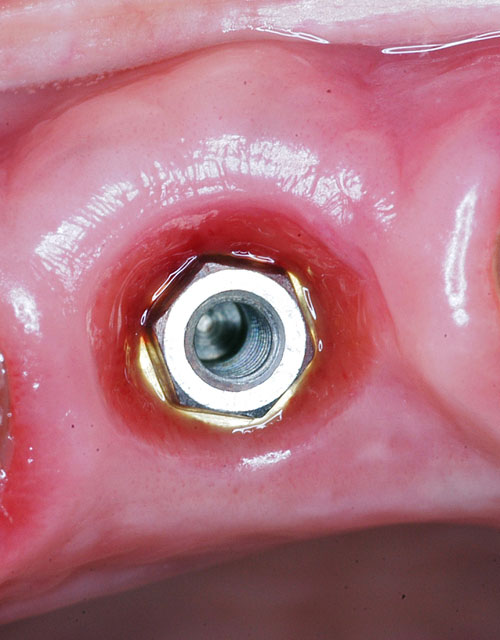

Mientras dichos movimientos ortopédicos se producen (período que supondrá otros seis meses), estudiamos los actos quirúrgicos a realizar en los cuatro implantes que pondremos. De acuerdo al estudio Desatascan realizado observamos tres situaciones diferentes: 1º-El Primer Molar Inferior Izquierdo, lo instalamos mediante Cirugía Minimamente Invasiva , con la aplicación de una Férula Quirúrgica Obtenida de los datos del scanner tratados con un programa de CMI (Cirugía Minimamente Invasiva), previa prueba en un modelo estereolitográfico, ya que la altura ósea era apenas de 9 mm. 2º- El Primer Molar Superior Derecho, se implantará mediante una ligera Elevación Atraumática (Trans alveolar) de Seno una vez logrado el espacio mesio distal necesario. 3º- El Incisivo Central Superior Derecho ausente, cuenta con un sustrato óseo prácticamente inexistente. El espesor de la tabla era de menos de 2 mm. Los caminos posibles a seguir para contar con una Rehabilitación de piezas independientes son dos: Optamos por esta segunda opción por ser menos cruenta y no necesitar de una zona dadora. Técnica esta que pondremos en práctica en dos etapas diferidas: 1º-Incisión horizontal palatinizada, incisiones peri rodetes gingivales e incisiones de descarga. Dilatación que comenzamos con dos incisiones de descarga sobre la cortical vestibular realizadas con disco. y el comienzo de la dilatación propiamente dicha mediante una hoja de bisturí, para luego seguir con un periostótomo . Recién después de alcanzada una cierta separación de la cortical vestibular de la palatina, empezamos con los dilatadores roscados. En este punto podríamos haber utilizado sin riesgos un Implante de 3,8 mm de diámetro, pero a fin de mejorar la estética del pilar emergente decidimos rellenar con material osteoconductor y osteoinductor (BiOss) y cubrir mediante membrana reabsorvible ( Bio Guide). 2º-Implantación seis meses después. Mientras se van cumpliendo los tiempos antes mencionados, y comprobamos reiteradamente la funcionalidad de la oclusión con los provisorios, tomamos impresiones definitivas y construimos primero el maxilar inferior, para definir en primer término la porción inferior de la Guía Anterior., y a nivel posterior Curvas y Microplanos. Para luego realizar los cuadrantes premolar- molar del superior: La espera de la regeneración ósea y sus tiempos pertinentes, más la espera de los tiempos de la implantación, nos obligaron a modificar las etapas del protocolo D.AT.O de manera de mantener la –D- mediante el sector superior de la GA. en provisorios, mientras fuimos resolviendo en forma definitiva los demás sectores. Ya pasados los meses necesarios para recrear un hueso adecuado en el área del Incisivo Superior Derecho, procedemos a resolver la implantación de dicha zona, observando que todo el esfuerzo dedicado al mismo había sido inútil, ya que la formación de hueso se produjo minimamente. Cuatro meses después tomamos impresiones del sector Antero Superior de la Guía Anterior, incluyendo el arrastre de un transfer . Seguimos modelando la encía con un nuevo juego de provisorios. Y se construye entonces el sector superior de la Guía Anterior. Se efectúa un control radiográfico a los 6 meses. Se ha intentado mostrar en esta Rehabilitación, que a pesar de las distintas circunstancias de cada paciente, siempre debemos tener en cuenta la necesidad de ejercer la DESOCLUSIÓN del caso como prioridad número uno, para luego perseguir la ALINEACIÓN TRIDIMENSIONAL de las arcadas y obtener así una OCLUSIÓN equilibrada. D.AT.O. ES EL PROTOCOLO QUE DEBEMOS SEGUIR EN TODA REHABILITACIÓN. BIBLIOGRAFÍA 1)William Mc Horris,B.S.,D.D.S. Oclusión. Con especial énfasis sobre :El rol funcional y parafuncional de los dientes anteriores. 2)Von Spee , Craff(Anatomista alemán, describió la curva de compensación de la articulación de molares y premolares).CURVA DE SPEE 1.89 3)Stuart,D.”Some aspects of the inervation teeth.”Procedings of Royal Society of Medicine.20:1675,19274)Muhleman,H. y Savdir,S”Tooth movility-its causes and significance”Journal of Periodontology ,36:153,Marzo ,Abril,1965. 4)Muhleman,H. Y Savdir,S”Toothmovility its causes and significance” Journal of Periodontology,36:153,marzo,abril,1965. 5-Oclusión y Diagnóstico en Rehabilitación Oral. 6-Anatomia Odontológica. 7-A contribution to the study of the movementes of the mandible. 8-Celenza F.W, Nadeskin J.F.,Oclusión.Situación actual. 9-D´Amico 10-Dawson P.E. 11-Huffman –Regenos. 12-Hobo S.-Takayama H.A. 13-Lucia V.O 14-Mc Horris. 15-Mc Horris. 16-Stuart C. 17-Vartan Veshnilian 18-Alvarez Cantoni H. AUTOR:Ratificación del Protocolo en Rehabilitación Bucal a pesar de las incidencias propias de cada caso clínico. A propósito de un caso.

Se construye inmediatamente un abuttment ceramizado para conformar la encía, y se prueban los núcleos de cerámica.